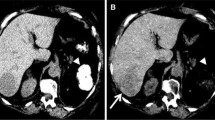

Delayed phase (DP) occurs subsequently to PVP, begins 100–120 s after CM injection, and is characterized by gradual CM distribution in the hepatic interstitial spaces. Consequently, attenuation differences between focal liver lesions and liver parenchyma are minimized (Federle and Blachar 2001). Main indications for performing a DP are the investigation of hepatocellular carcinoma (Furlan et al. 2011), cholangiocarcinoma, and detection of liver metastases (Kanematsu et al. 2006). In clinical routine it is also useful to characterize cavernous hemangiomas, identified by the typical centripetal enhancement pattern (Kim et al. 2001). Figure 1 provides an overview of the different phases routinely acquired in liver imaging.

Multiphasic liver CT examination. (a) Unenhanced phase demonstrates slightly higher parenchymal density than the portal venous system. A microcalcification is also easily identifiable. During late hepatic arterial phase (b) the aorta and the hepatic artery are the vessel characterized by the highest attenuation values, while portal vein and liver parenchyma enhance to a lesser degree. Subsequent portal venous phase (c) maximizes portal vein attenuation and liver enhancement, while the hepatic artery density is reduced. During delayed phase (d) the contrast medium is distributed in the hepatic interstitial spaces, and thus the attenuation differences between vessels and liver parenchyma are reduced